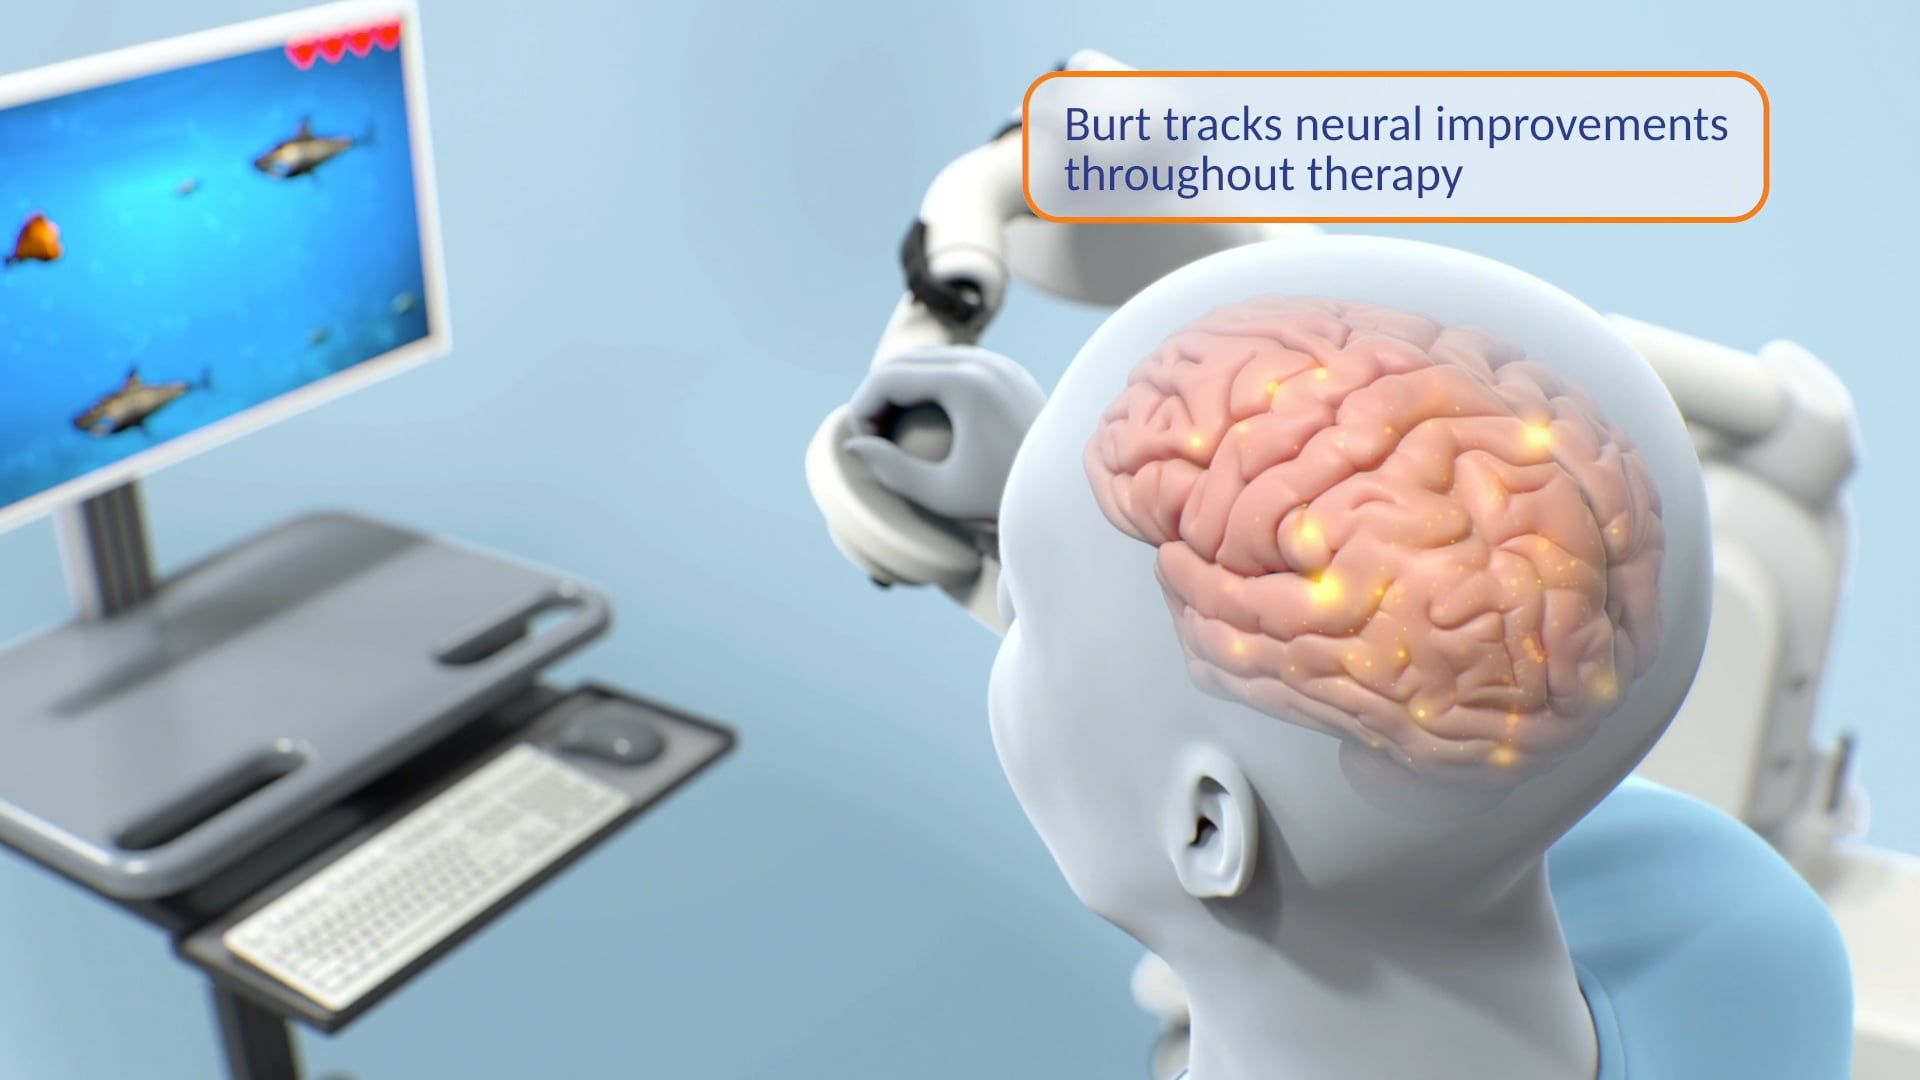

Medical Training

Medical Animation

Neurology